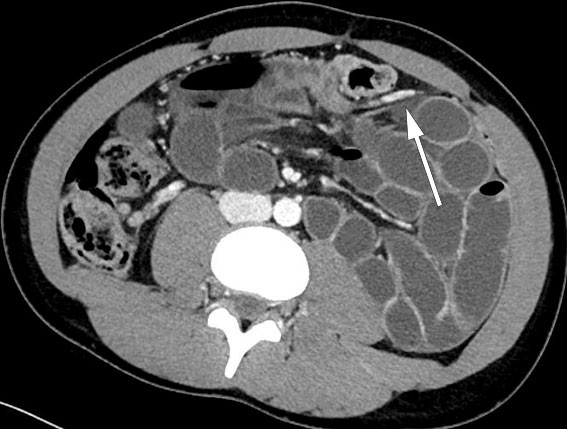

CT-undersøkelsen viste dilatert tynntarm med brå kaliberveksling sentralt og til venstre i buken, stedvis sløring av krøset mot utvidet tynntarm og fekalisert tynntarmsinnhold. Det var ikke mistanke om tarmiskemi, og man så ikke fri luft eller væske intrabdominalt. Samlet radiologisk vurdering ga mistanke om adheranseileus, noe som ikke passet helt med pasientens alder og fravær av tidligere abdominalkirurgi.

I generell anestesi fant vi ved laparoskopi sparsom fri væske i bukhulen. Store deler av tynntarmen var dilatert. Vi begynte å reponere tynntarmen mot høyre, først fra proksimalt mot distalt og deretter fra ileocøkalovergangen mot proksimalt. Vi fikk inntrykk av at tynntarmen var herniert innunder en «streng» i tilknytning til venstre colon. Ved nærmere ettersyn kunne man skimte vaskulære strukturer, og et tynt og defekt mesenterium kunne ikke utelukkes (figur 1). Grunnet mye dilatert tarm i feltet, begrensede plassforhold og usikkerhet om hvorvidt all tarm var reponert, valgte vi å konvertere til laparotomi. Med midtlinjetilgang fant vi mekanisk tynntarmsileus fra en venstresidig paraduodenal herniering med store deler av tynntarmen herniert mot venstre dorsalt for vena mesenterica inferior. Tynntarmen som ble reponert, framsto som viabel, da det var god tarmmotilitet og god blodsirkulasjon. Det ble satt fortløpende suturer med patent lukning av åpningen i mesenteriet, uten skade av karstrukturene.

Ved regranskning av pasientens CT-bilder forløp v. mesenterica inferior ventralt for de hernierte tynntarmsslyngene. Dette ble også sett peroperativt og samsvarte med diagnosen paraduodenalt brokk (figur 2)